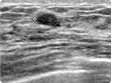

| 16 | 복부 초음파 검사 | 검진동 4층 | 약 15분 | 간, 담도, 신장, 췌장, 비장 등의 질환 |   |

| 17 | 갑상선 초음파 검사 | 검진동 4층 | 약 15분 | 갑상선비대증, 갑상선암 및 기타 이상질환 |    |